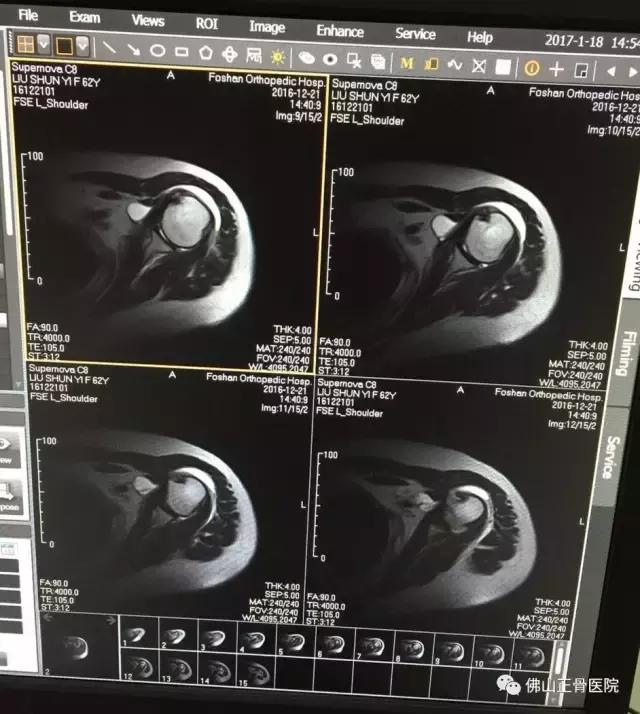

MR示:患者左肩关节改变,冈上肌肌腱撕裂,左肩关节腔内有积液,右下盂唇前方有少量积液,诊断为肩袖损伤。

62岁的刘女士,家住广州。2015年12月中旬,在家中跌倒后出现了左肩剧痛,左臂上举困难。疼痛严重时不能左侧卧位,明显影响睡眠和穿衣等日常活动,到了医院拍X检查,寻找受限原因,却没有发现“骨质异常”,通俗地说,就是没有伤到骨头。

既无外力损伤,又找不到有效的治疗方法,百愁莫展的刘女士来到佛山正骨骨科院康复科就诊。负责接诊的康复科副主任曾彦经询问病史、体格检查,并为刘女士进行左侧肩关节的肌骨超声影像检查。

原来困扰刘女士的症状为左肩袖损伤。在超声仪器下,曾主任看见了刘女士肩膀下面的肌腱撕裂和积液,确诊病因后,他随即为刘女士做了超声介导下注射治疗。后经综合治疗2周后,刘女士左肩疼痛基本改善,穿衣等日常活动也恢复正常。